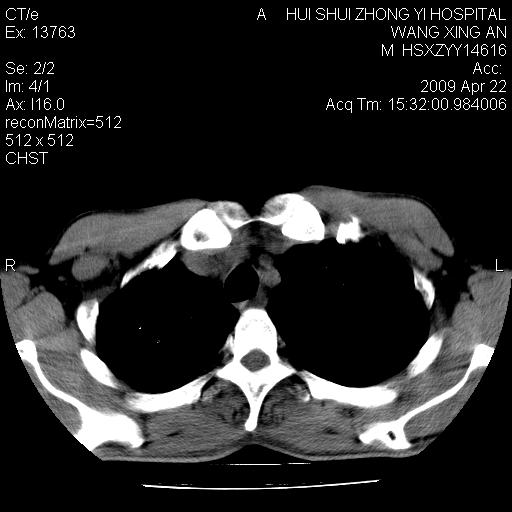

标题: CT19534:患者男、46岁咳嗽、胸痛半月。 [打印本页]

标题: CT19534:患者男、46岁咳嗽、胸痛半月。

1、右下肺中央型肺癌并右肺转移,右肺中下叶不张。(右肺有结节影)。胸骨转移

2、右中上肺陈旧性肺结核(因为大多为纤维灶)。

3、右侧胸腔积液。